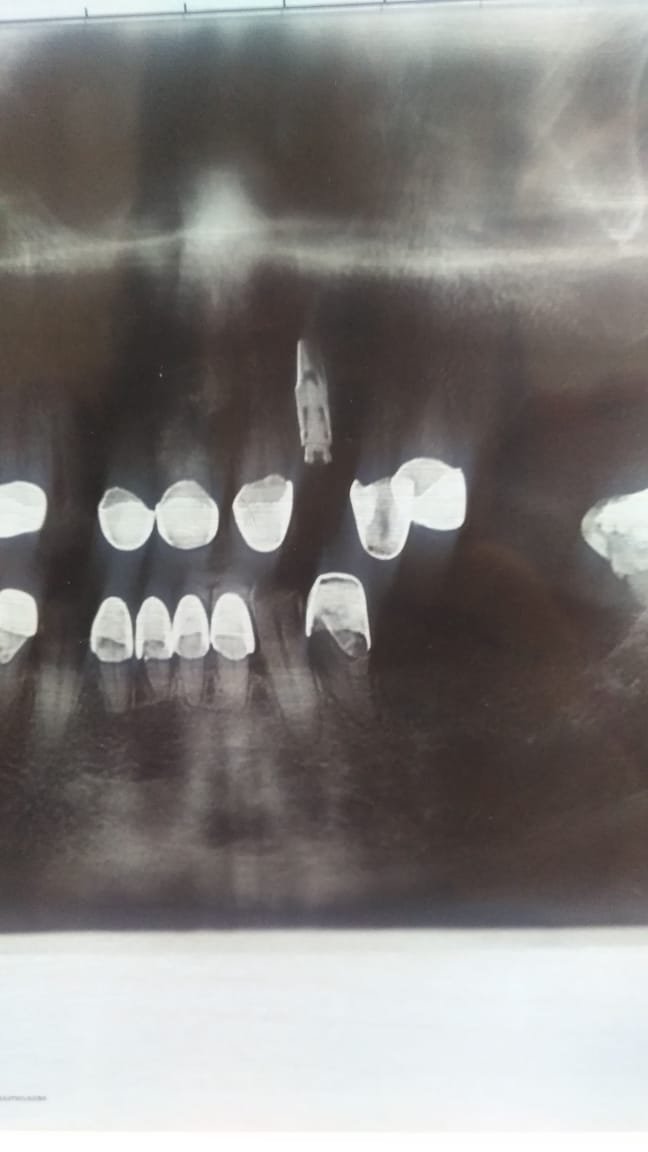

implantes

Me gustaría saber si alguién sabe de que marca son estos implantes,ya que han venido a mi consulta dos pacientes con los implantes sin rehabilitar,y la clinica donde se los [...]